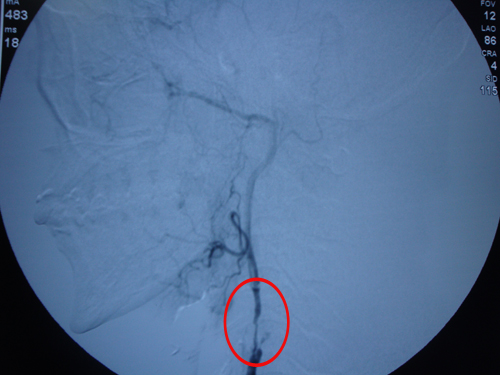

DSA示:左侧颈内动脉闭塞,颈外动脉有部分血流通过。

该患者左侧颈内动脉已经闭塞,颈外动脉尚有部分血流通过,故行颈外动脉内膜剥脱术。2010年5月24日,由协作组张勤奕教授、美方组长Douglas医生共同为其实施了左侧颈外动脉内膜剥脱术+血管成形术。